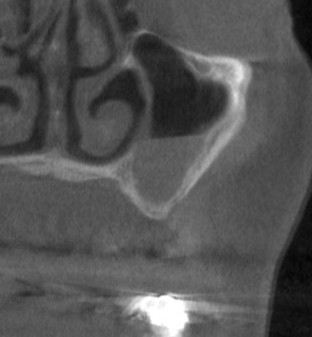

そこで、まず、2本目、3本目の部位に、サイナスリフトという上方の空洞に人工骨を填入する骨造成術を行いました(下の写真、3段目)。